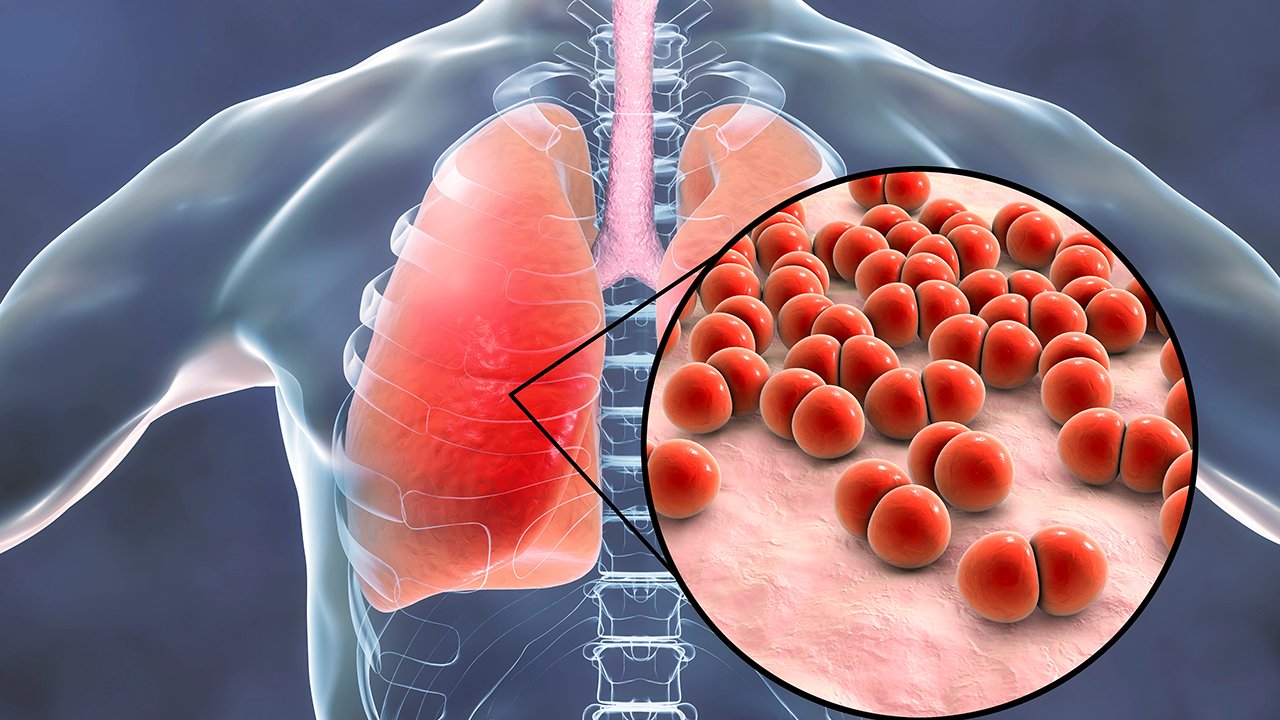

Фотографии бактерий, вызывающих бактериальные пневмонии у животных